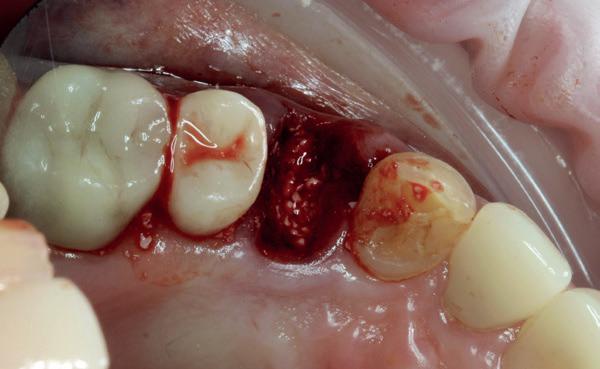

De implantaatplaatsing en de beslissende fout (afbeelding 1-13)

De extractie verliep voorspoedig, waarbij ik zoals al-

tijd probeerde de buccale botlamel intact te houden. Dit is cruciaal voor latere botbehoud en implantaatplaatsing. Na curettage en spoelen van de alveole beoordeelde ik de situatie opnieuw: de botcondities leken gunstig voor een immediaat implantaat.

1. Afgebroken 24. Geen hoektandgeleiding aanwezig.

2. Decapiteren van het element en splitsen van de wortels.

3. Verwijderen van de radices.

4. Curettage en spoelen met een zoutoplossing.

5. Het ridge preservation protocol waarbij we proberen zoveel moge-

lijk bot te behouden met behulp van een xenograft.

6. De tijdelijke pontic, waarbij gebruikgemaakt wordt van de eigen afgebroken kroon en wat composiet. 7-10. Een full thickness flap osteotomie met hand plaatsing van een MegaGen AnyRidge Implantaat volgens protocol resulteerde in een

primaire stabiliteit van 60 Ncm.

11. Röntgenfoto ter controle van de plaatsing en de angulaire. Dit bone-level implantaat werd 4 mm onder de weke delen geplaatst.

12. Direct post-op. Een direct geplaatste tijdelijke kroon. Vastgezet met een torque van 20 Ncm en gehecht met prolene 5/0.

Hier begon echter de cruciale fout in mijn klinisch besluitvormingsproces. In mijn streven naar maximale primaire stabiliteit - wetende dat immediaat belasten enkel mogelijk is bij hoge stabiliteit -on-

13. Röntgenfoto ter controle van de pasvorm van de direct geplaatste tijdelijke kroon.

derprepareerde ik de osteotomie. Dit betekende dat ik een iets te smal implantaatbed creëerde, in de hoop dat het implantaat stevig in het bot verankerd zou worden.

Op papier leek dit een logische stap: het MegaGen AnyRidge-implantaat dat ik koos, gaf me een stabiliteit van 60Ncm—een cijfer dat vertrouwen gaf in immediaat belasten. Maar in mijn enthousiasme had ik onvoldoende rekening gehouden met de biologische gevolgen van overmatige compressie.

Door de te hoge druk op het omringende bot verminderde daarin de doorbloeding, wat leidde tot een verhoogd risico op botnecrose. Dit was geen fout van abutmentkeuze of occlusie; dit was puur het gevolg van mijn drang naar optimale stabiliteit en de wens om het implantaat direct te belasten, onder invloed van patiëntdruk.